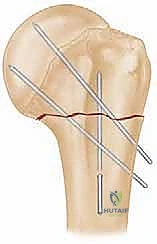

4. إدخال الأسلاك المعدنية (K-wires)

بمجرد أن يصبح الكسر في الوضع المثالي، يتم إدخال أسلاك كيرشنر (Kirschner wires) الدقيقة عبر الجلد مباشرة إلى العظم. يتم توجيه هذه الأسلاك بزوايا هندسية مدروسة لضمان أقصى درجات الثبات. عادة ما يتم استخدام 2 إلى 4 أسلاك.

5. التحقق من الثبات وقص الأسلاك

بعد وضع الأسلاك، يتم تحريك الكتف بحذر للتأكد من ثبات الكسر التام. بعد ذلك، تُقص نهايات الأسلاك وتُترك بارزة قليلاً فوق الجلد (أو تُدفن تحت الجلد مباشرة) لتسهيل إزالتها لاحقاً.